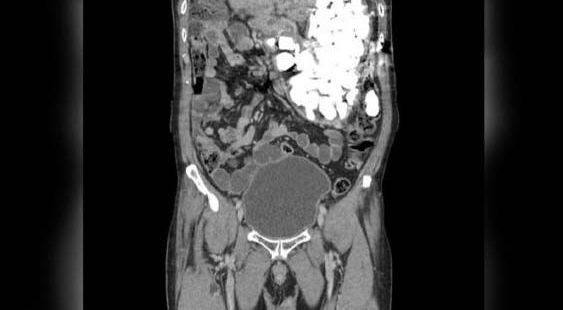

El asiático tuvo que ser intervenido qirúrgicamente. Crédito: (Journal of Medical Case Reports,)

El cirujano Pyong Wha Choi dijo a la revista Journal of Medical Case Reports, que el paciente llegó a mediados de enero hasta la sala de emergencia del centro médico, y, tras realizarle una radiografía se detectó el material en el estómago.

El asiático tuvo que ser intervenido qirúrgicamente por la gran cantidad de elementos en su estómago.